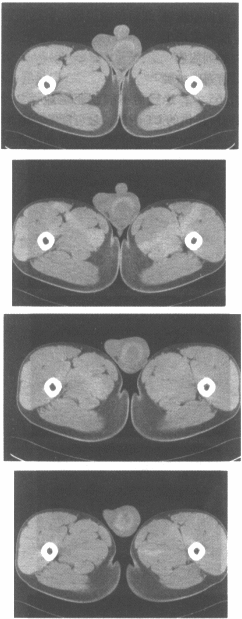

男,20岁,外伤1天,左侧阴囊肿痛,结合CT平扫图像,最可能的诊断是

• A.睾丸血肿

• B.睾丸肿瘤

• C.睾丸囊肿

• D.腹股沟疝

• E.睾丸炎